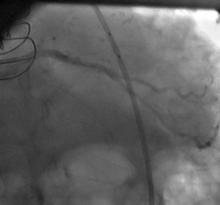

1) LM: subtotal ISR lesion (figure 2, figure 3)

2) LAD: occluded at the ostium and filled via LIMA

3) LCX: proximal non-significant lesion

4) RCA: mild diffuse disease